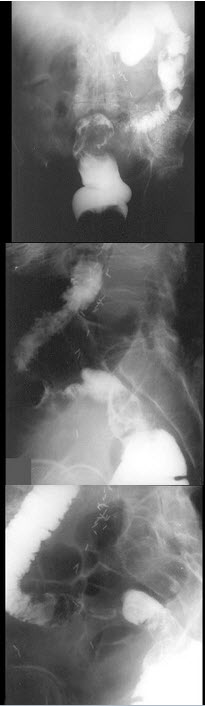

25、单项选择题

女,50岁,血便10余年,加重1年(连续出血),近2月大便时肛门常滴鲜血,量较多,X线检查如图,最可能的诊断是()

A.直肠癌

B.直肠绒毛状腺瘤

C.直肠淋巴瘤

D.直肠转移癌

E.直肠结核